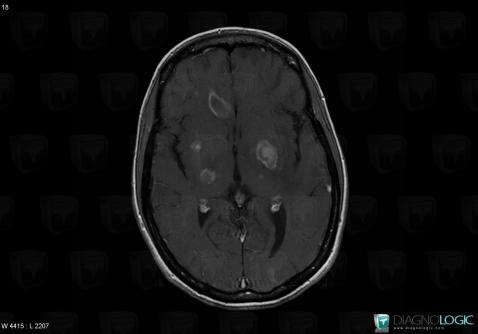

Toxoplasmosis, Cerebral hemispheres, MRI

Here is the specific information in the key image above:

- Diagnosis Toxoplasmosis (link to Abscess), Location(s) Cerebral hemispheres, with gamuts Intracerebral lesion with intense enhancement